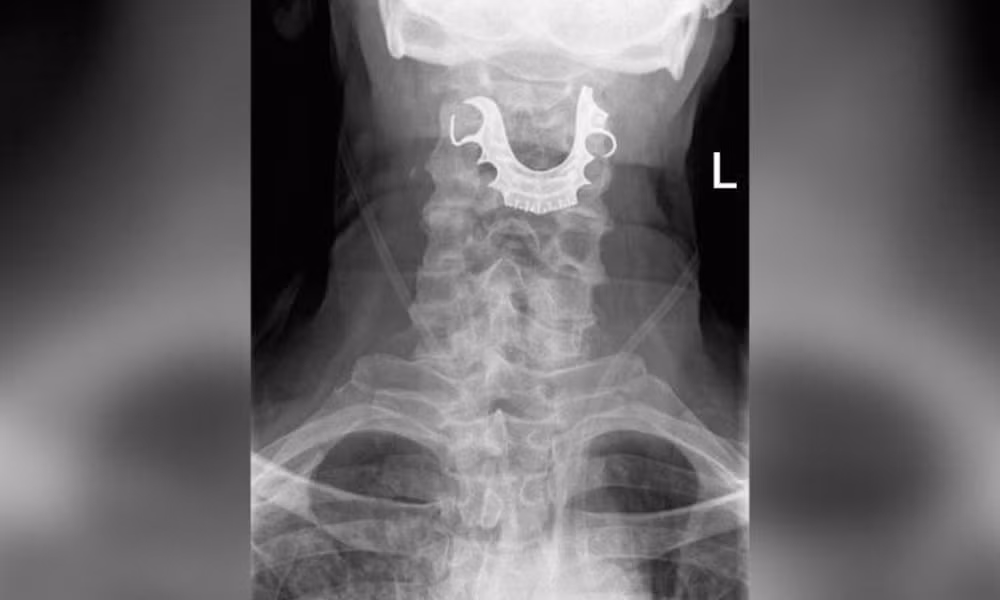

| Phim chụp hàm răng giả mắc trong cổ họng bệnh nhân. |

Cuối cùng, liệu trình chẩn đoán đã xác định được một vật thể hình bán nguyệt nằm chặn ngang dây thanh quản của ông, gây ra các vết xước và sưng tấy trong vòm họng. Người đàn ông đã được đưa vào phẫu thuật khẩn cấp để gỡ bỏ hàm răng giả. Ông đã phải ở lại bệnh viện trong 6 ngày sau đó.